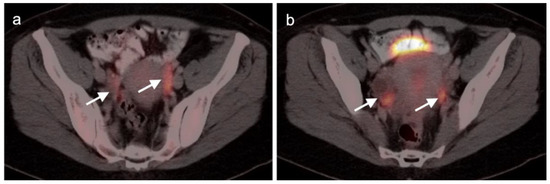

2.4. Cervical Cancer